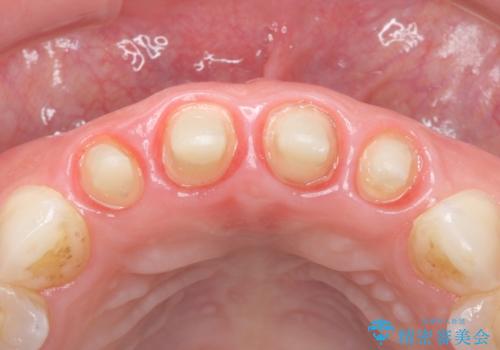

- 10年前に美容外科クリニックで前歯を治療したところ、あまりに不自然で逆にコンプレックスになってしまったことを主訴に来院された患者様です。

前歯4本の被せものは連結されており、不自然なだけではなく清掃性も悪く歯茎が著しく腫脹していました。

歯茎の腫脹が顕著であったため、適合の良いオーダーメイドの仮歯に変え、歯茎の状態が良くなるまで1ヶ月待ったのち型取りを行いました。